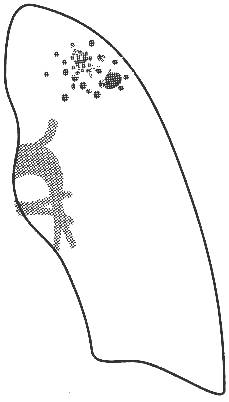

Рис. 4 Рентгенограмма ОГК и схема к ней левого легкого.

В апикальном отделе S1–2 левого легкого определяется обогащенный легочный рисунок за счет множественных полиморфных преимущественно среднеочаговых теней, склонных к слиянию с нечеткими контурами; здесь же имеются плевроапикальные наслоения. Корни легких структурны, не расширены. Купол диафрагмы четкий, синусы свободны.

Заключение: Очаговый туберкулез в S1–2 левого легкого в стадии инфильтрации.